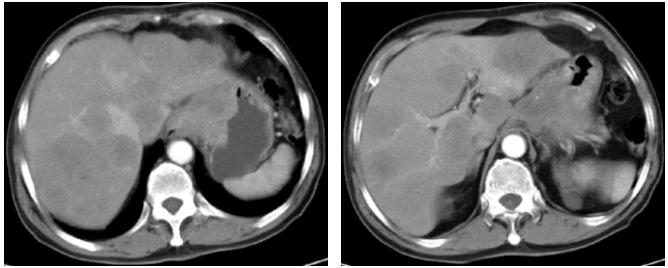

2022-1-18上腹部CT:1. 食管胃底交界-胃小弯壁明显增厚,侵犯胃壁全层,突破浆膜层伴腔外软组织肿块形成,最大横断面(胃小弯)约49×64 mm,考虑胃癌;2. 肝胃韧带、肝门区、腹膜后、右心膈角、纵膈内多发肿大淋巴结,较大21 mm,待排转移性淋巴结;3. 肝内多发转移瘤,较大位于肝S7,大小约66×82 mm。

2022-4-13复查上腹部CT(3疗程后):符合贲门-胃体癌表现,伴肝内多发转移瘤,病灶均较前明显缩小,疗效评价PR。